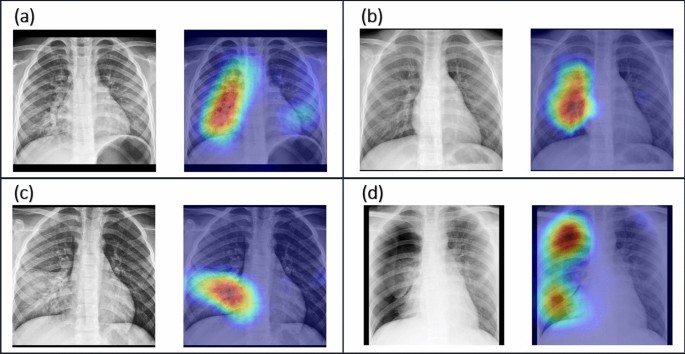

This chest X-ray shows an area of lung inflammation indicating the presence of pneumonia. However chest X-ray examinations for pneumonia detection are prone to subjective variability 2 3. Please see disclaimer on my website.

Applied Sciences Free Full Text Visualization And Interpretation Of Convolutional Neural Network Predictions In Detecting Pneumonia In Pediatric Chest Radiographs Html